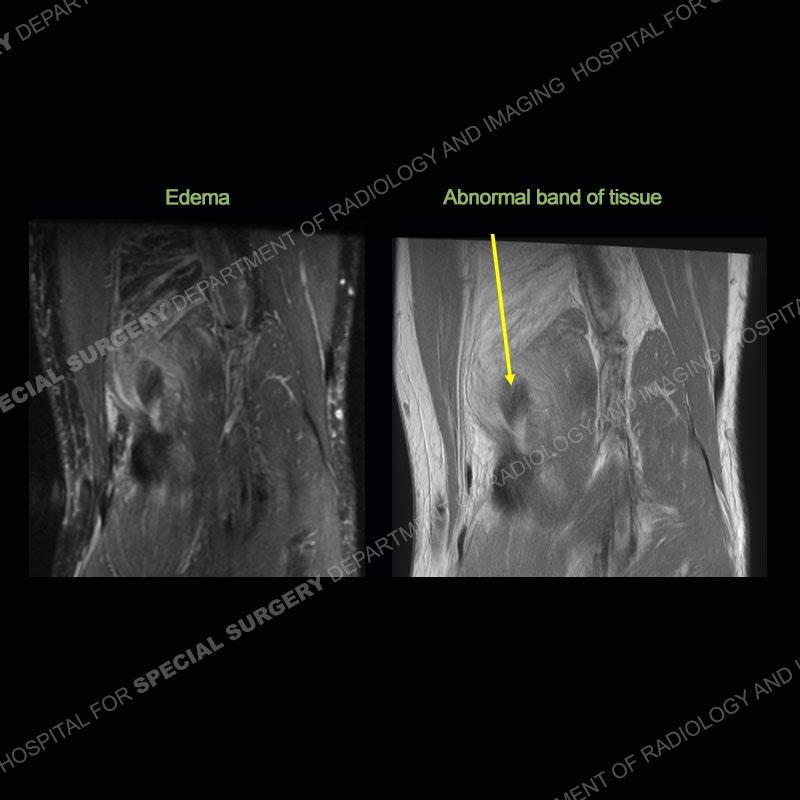

The radiographs show degenerative change of the medial compartment and a varus knee, but they are not germane to this case. No acute bony injury is present. The MRI shows edema of the posterior medial knee/soft tissue and a focal area of a partially disrupted low signal structure. The details are kept at a minimum in the findings of this case on purpose.

Diagnosis: Partial Disruption Medial Head Gastrocnemius (MHG)

The findings were kept purposefully vague as identifying the structures early on takes away a lot of the diagnosis. An uncommon entity and one of which we do not see a lot. Enthesopathic changes and tendinosis are seen as are distal MHG injuries, but proximal tears are rarely present. This case highlights a number of points. One, it almost always comes down to anatomy. Perhaps not a structure we normally spend too much time on, except save for diagnosing a Baker’s cyst, but knowing where this structure and all structures exist in all three planes is imperative. Second, when you think you are making a “call” or finding that you have never made before, step back and think is this just the abnormal presentation of a common pathology. That situation arises much more frequently. Third, if you look at it once, twice, and probably a third time and are confident in your odd or very rare diagnosis, stick to your guns. Especially, when it comes down to anatomic structures, the proof will be in the images.

Fourth, use all imaging planes and different pulse sequences to make your diagnosis. The edema highlighted in this case can be seen as the obscuration of fat on the PD images but is much easier to perceive as the high signal on the IR pulse sequences. The actual disruption of the MHG myotendinous junction is only able to be seen on the axial images. On the sagittal and coronal images, we get a sense something is wrong but hard to be exact. Lastly, when you look at a study and something just seems off (as I would say the sagittal and coronal images do with that dark band of tissue posteriorly), listen to yourself and go through the study slowly and meticulously. Most of the time you will find you were right, and something indeed is present.